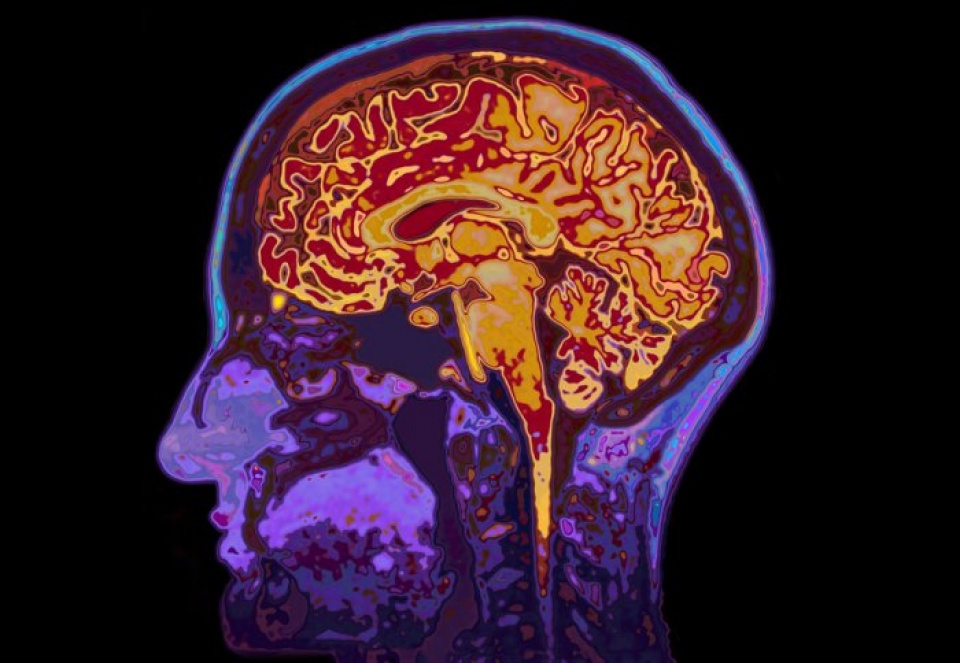

Gien này có tên là PGC1-alpha, có thể ngăn chặn sự hình thành một loại protein có tên là cầu nối amyloid-beta, thành phần chính của các mảng protein amyloid trong não của những người mắc bệnh Alzheimer. Các nhà khoa học đã tiêm loại virus có chứa gien trên vào hai khu vực có liên quan đến trí nhớ ở những con chuột bị bệnh Alzheimer giai đoạn đầu là chân hải mã và vỏ não, những khu vực đầu tiên có sự hình thành các mảng protein amyloid.

Sau 4 tháng theo dõi, họ thấy trong não của những con chuột có gien PGC1-alpha có rất ít các mảng protein amyloid so với những con chuột không có gien này. Ngoài ra, trí nhớ của những con chuột có gien trên đã được cải thiện.

Cũng trong nghiên cứu trên, các nhà khoa học nhận thấy rằng các tế bào trong não của những con chuột có gien PGC1-alpha không bị chết và số lượng tế bào thần kinh đệm nơi bệnh Alzheimer thường giải phóng các chất độc gây tổn hại cho các tế bào não, đã giảm xuống.